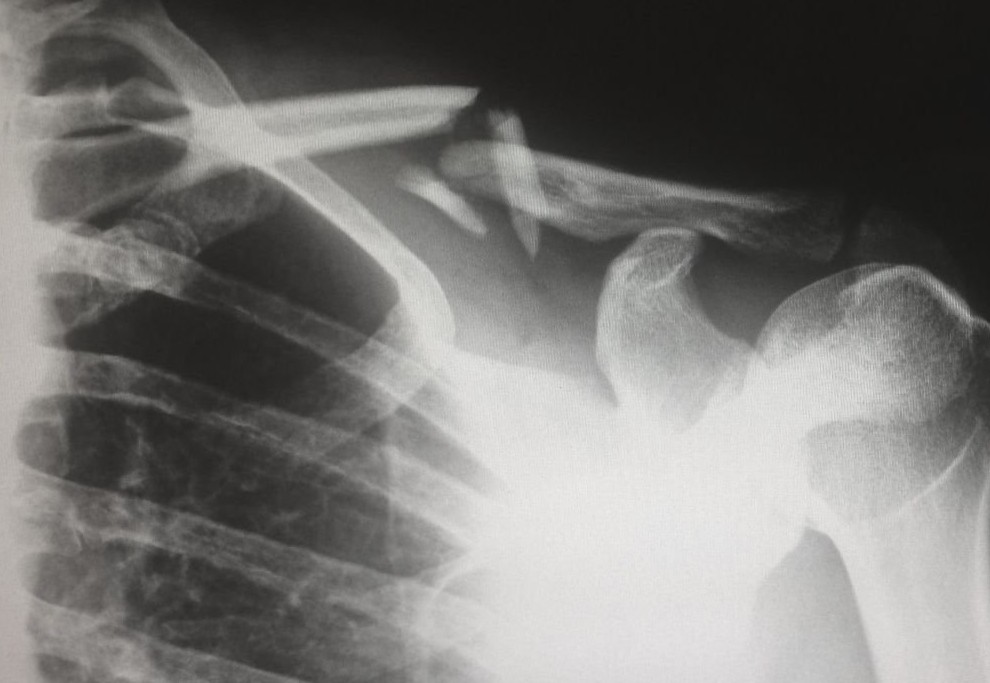

Опухоль, которая распространилась на кости, может привести к повреждению и ослаблению костей, а также вызвать сильную боль. Это еще больше увеличивает вероятность перелома. Важно отметить, что наличие симптомов гиперкальциемии не обязательно означает, что у вас запущенный рак кишечника. Но следует особенно насторожиться при появлении других коварных симптомов: